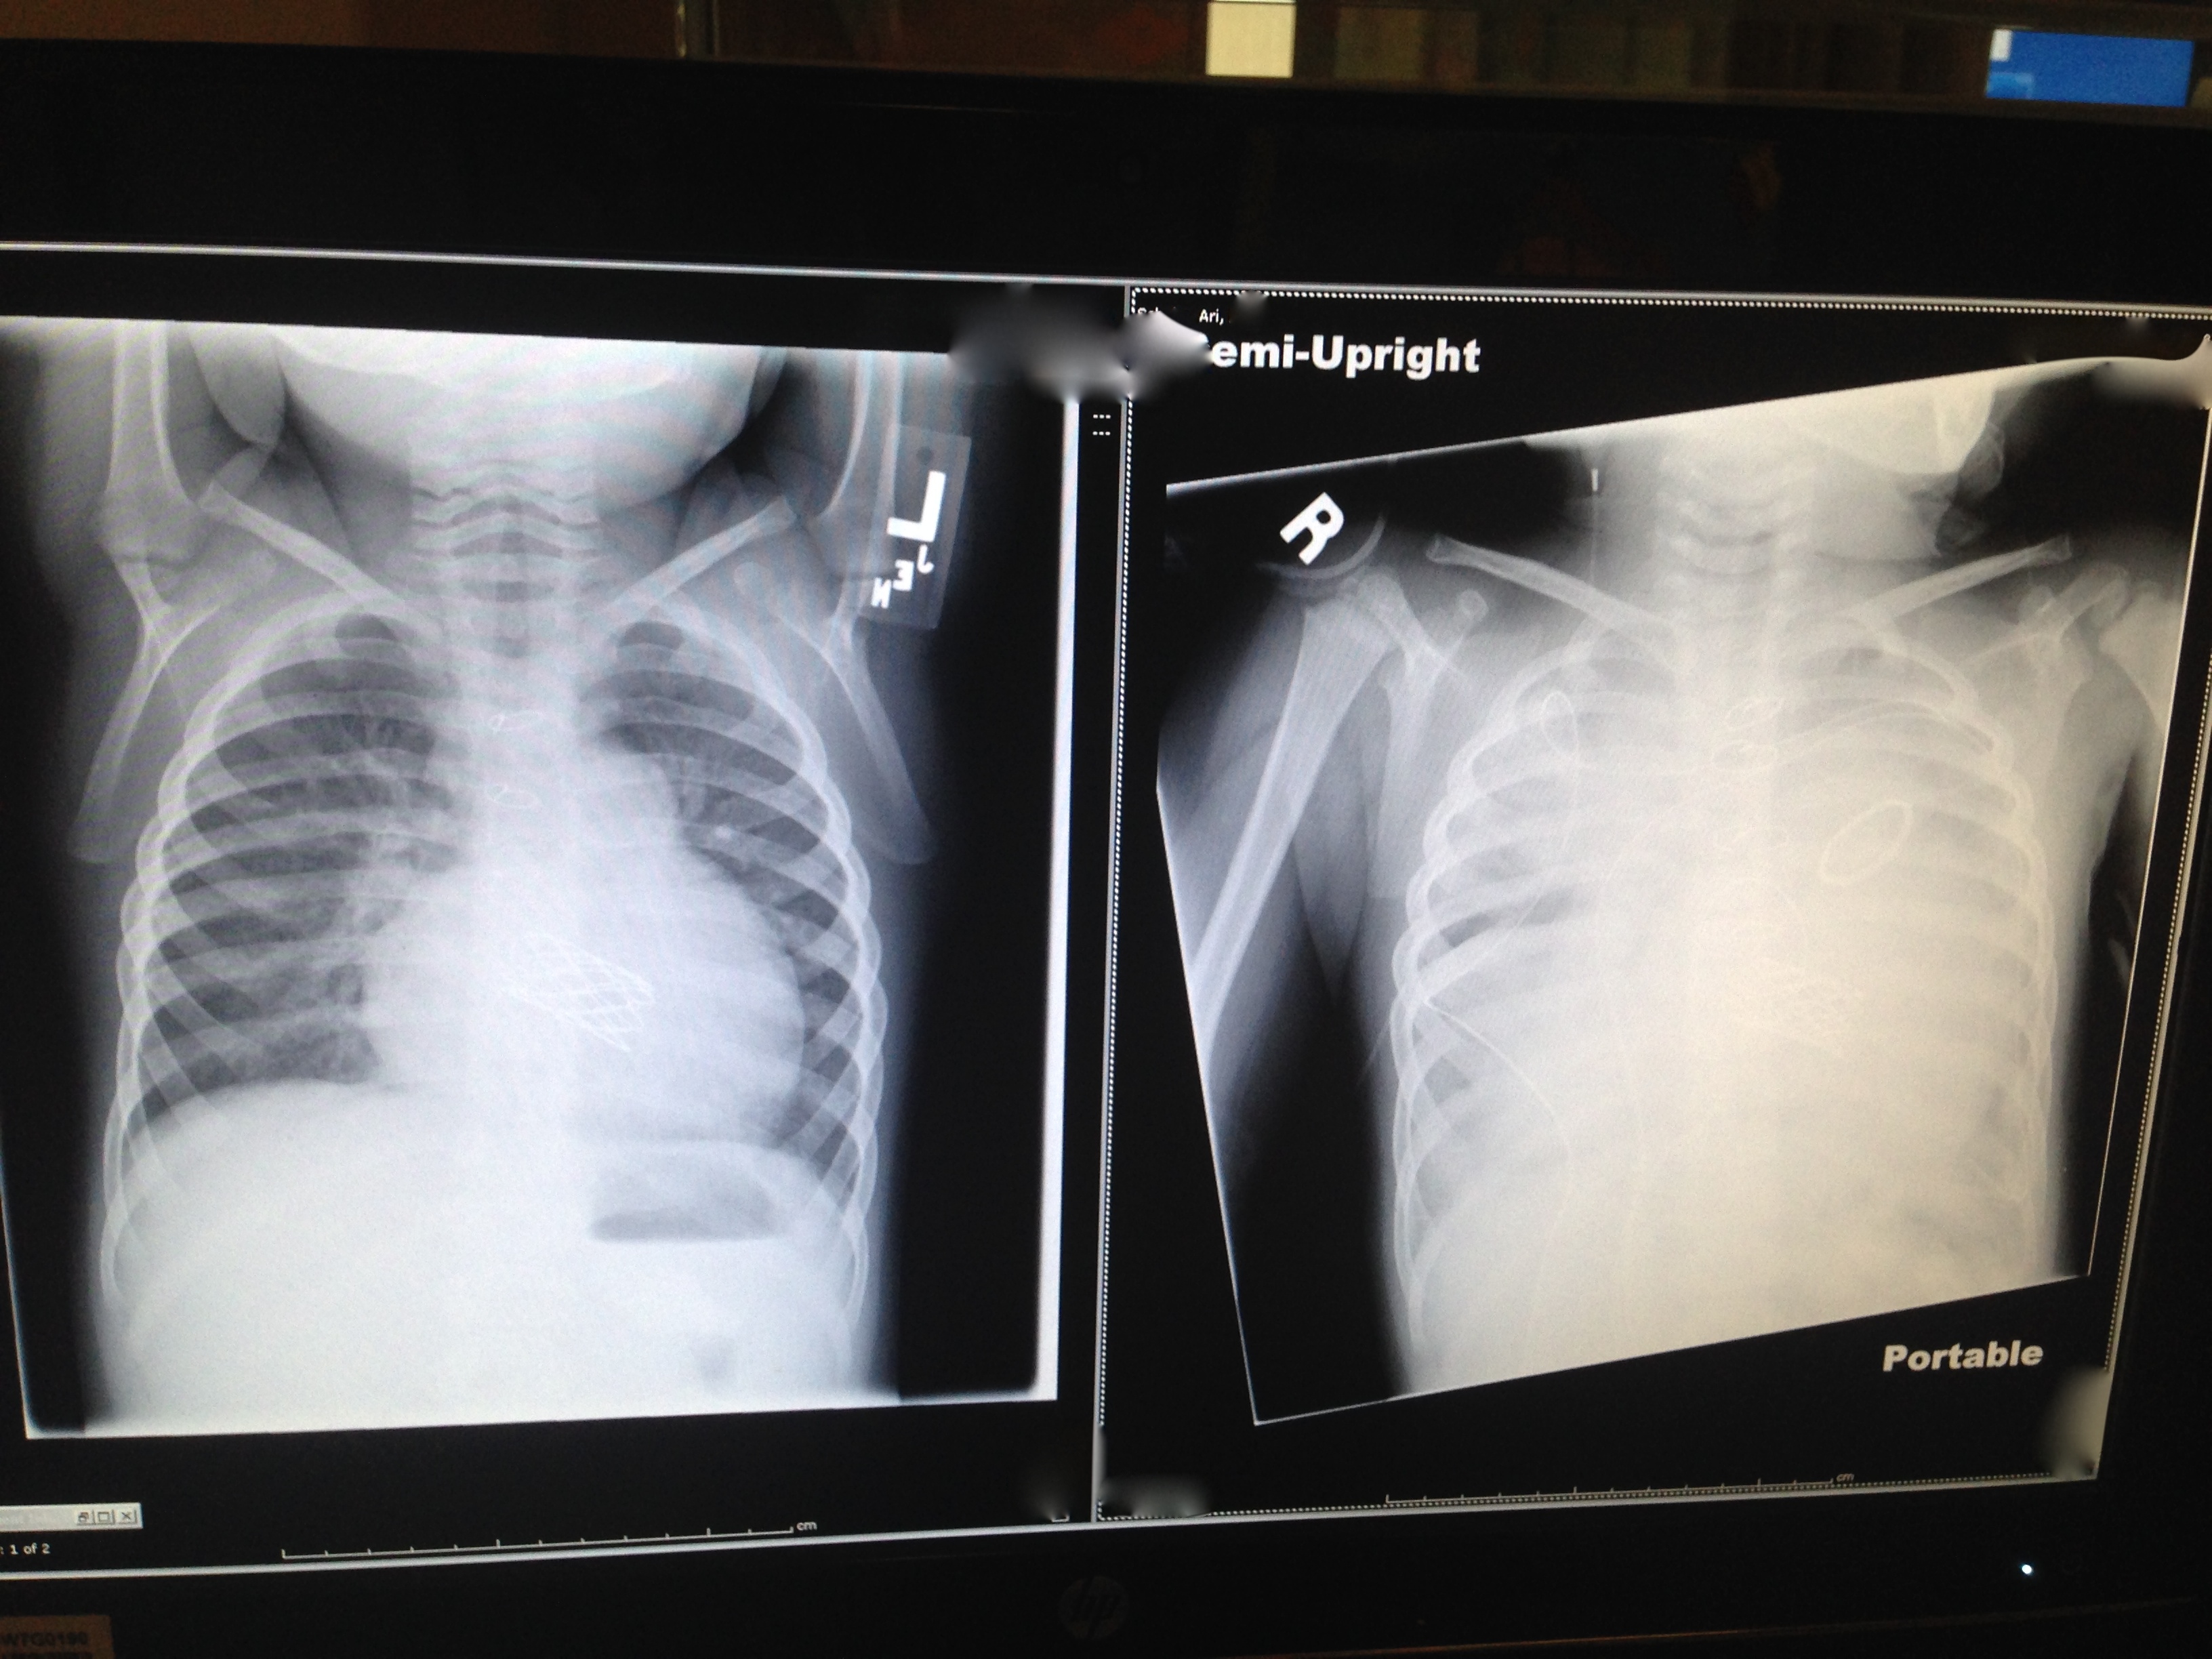

Worst of all, his lungs were so wet they looked snow white. On the left is his pre-op x-ray. The white shape in the middle is the outline of his (enlarged) heart. The black spaces between the ribs on the left and right indicate clear lungs.

On the right is his ‘snow white’ post-respiratory crisis x-ray. During the crisis, his lungs were so wet, he was foaming at the mouth.